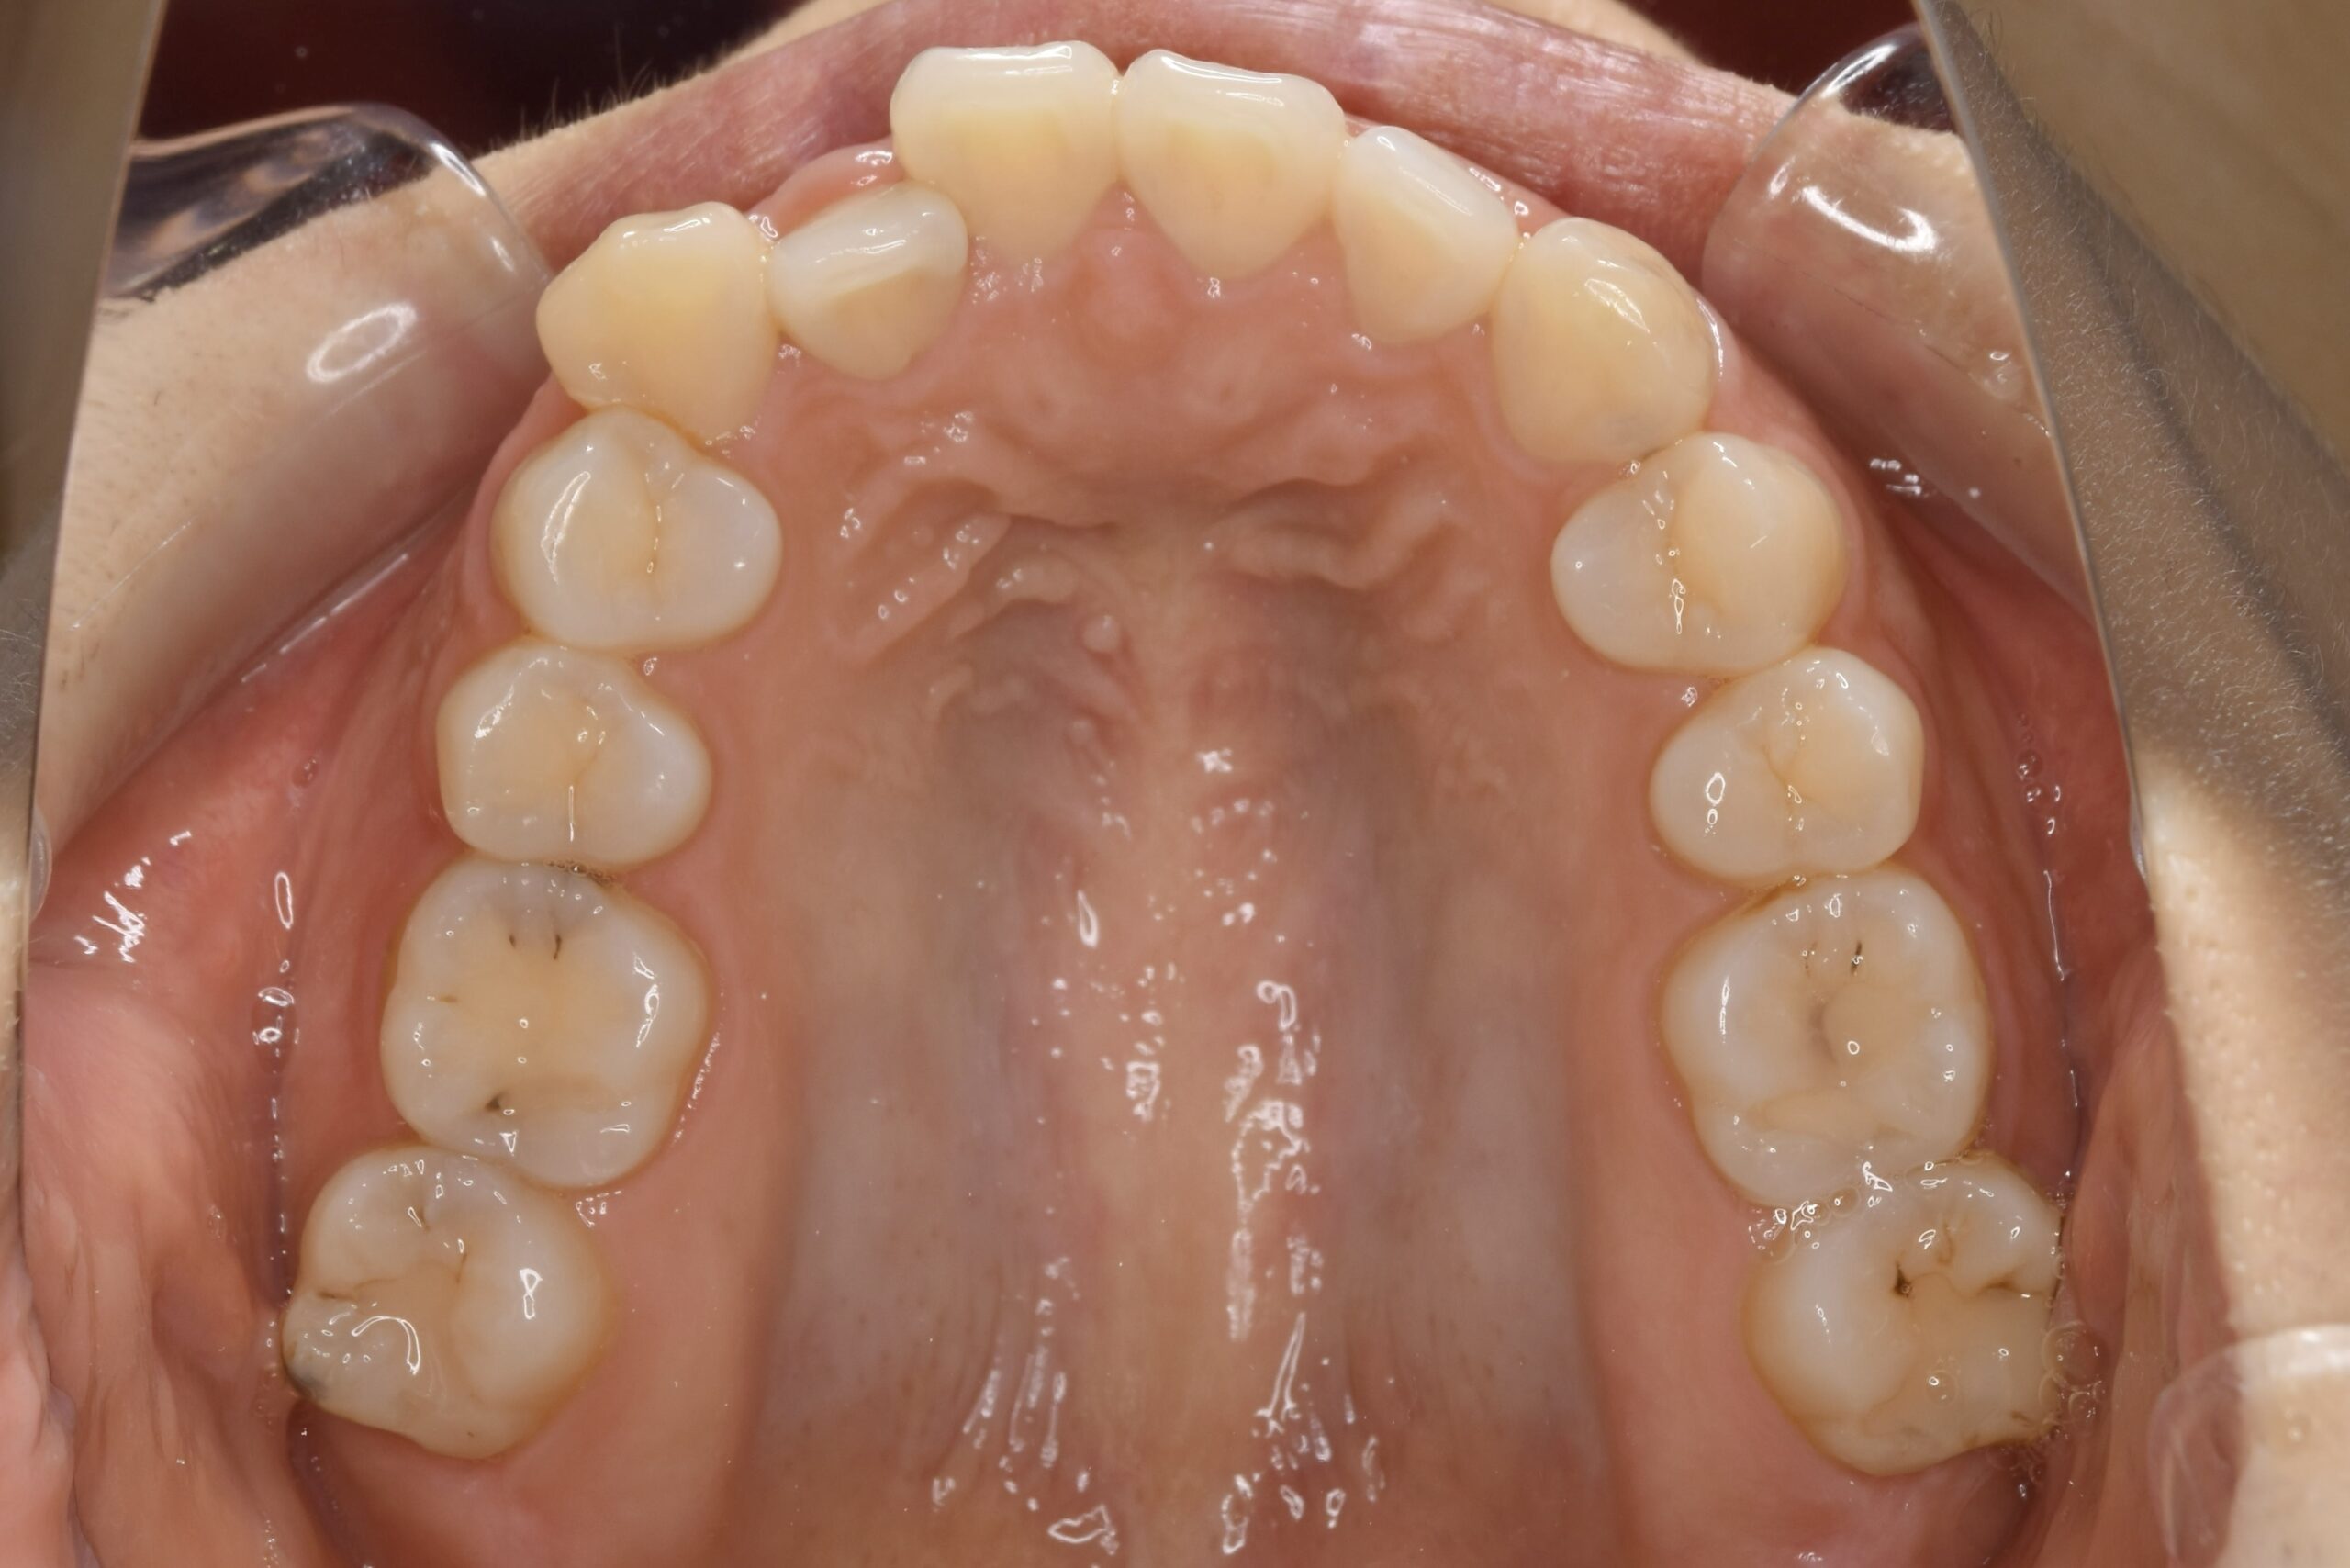

32歳 女性 治療期間:1年7ヶ月

BEFORE

診断名・主な症状 叢生を伴う上顎前突

治療内容 上下とも歯を2本抜いて、上の前歯を後方に引きながら、でこぼこを治しました。

使用装置 マウスピース矯正装置(インビザライン)

抜歯部位 上 両側4番目

下 右側4番目、左側5番目